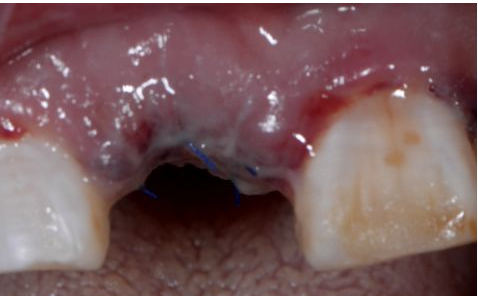

植入后縫合

術后三天

在口腔種植領域中,由于各種原因造成的種植牙局部牙槽突骨量不足或種植體周圍骨缺損的修復在種植外科的研究中已經取得了重大突破。新一代的血漿提取物--濃縮生長因子(CGF,Concentrate Growth Factors)能夠明顯縮短術區成骨的時間,提高成骨質量,促進成骨及組織的愈合;具體有:引導骨再生技術、聯合骨膜表面覆蓋加速軟組織愈合、用于上頜竇提升、拔牙后即刻種植、牙槽嵴位點保存、頜骨囊腫的治療、牙槽骨修整。